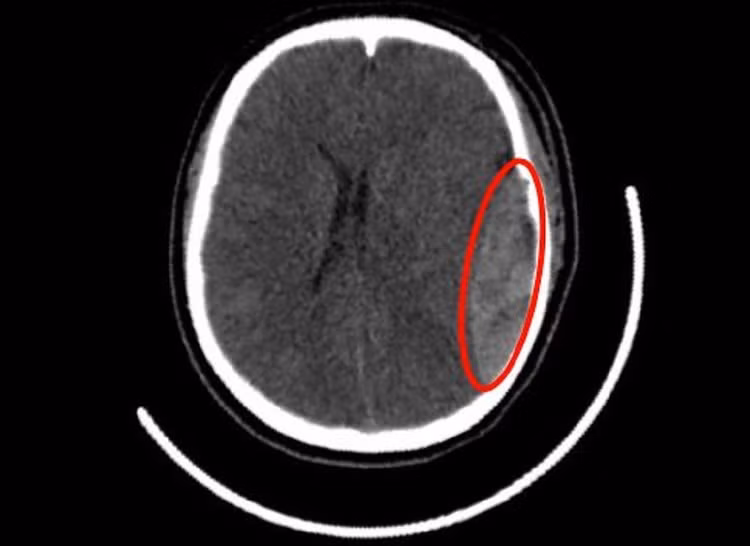

Tại đây, các bác sĩ nhanh chóng thăm khám và ghi nhận người bệnh yếu nửa người bên phải, điểm tri giác theo thang Glasgow là 9-10/15. Chụp MSCT sọ não cho thấy một khối máu tụ ngoài màng cứng ở bán cầu não trái lan xuống cực thái dương trái, kèm theo nứt xương sọ vùng thái dương trái.

Hình ảnh kiểm tra ghi nhận vị trí nứt hộp sọ, máu tụ dưới màng cứng nữ sinh gặp phải/Ảnh tienphong.vn